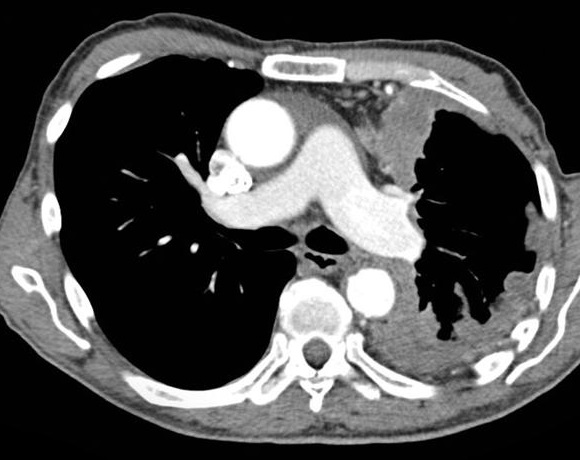

Mệme cas en coupe TDM axiale

avec aspect radiologique en plaque diffuse

hyperdensite de la plevre du poumon droit . Poumon

droit est en un peu de restrictive par la lesion de

tuberculose |